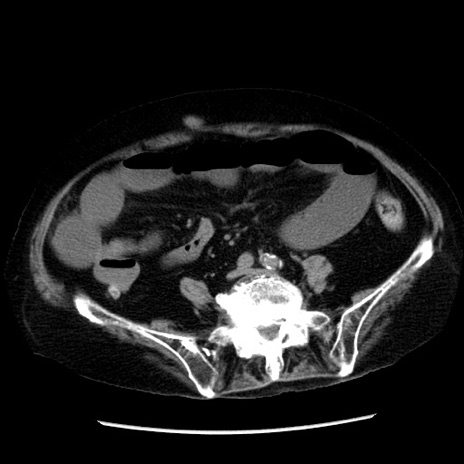

症例14(横断像)

【症例】 90歳代女性

【主訴】 腹痛・嘔吐

【現病歴】今朝から左側腹部痛を認めた。 経過観察していたが、嘔吐を認めたため来院。

【既往歴】 子宮癌術後

【身体所見】 意識清明、BP 127/54mmHg、P 98bpm Sp02 95%(RA)、BT 35.8°C、腹部平坦・軟腸ぜん動音聴取良好、右下腹部圧痛(+) 反跳痛なし

【データ】WBC 9800、CRP 0.46